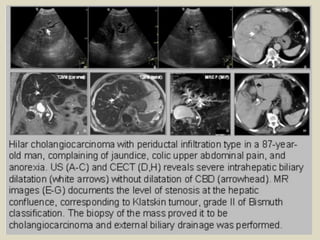

Hilar cholangiocarcinoma The most common

location for cholangiocarcinoma is either at the

confluence of the right and left hepatic ducts, or at

the proximal CHD, and has been termed a ''Klatskin

tumor.'' These tumors can be small and difficult to

visualize early at imaging. Hilar

cholangiocarcinoma can usually be differentiated

from adjacent adenopathy or extrinsic masses

causing biliary obstruction due to the latter

causing compression and displacement of the duct.

Occasionally large masses can envelope the biliary

tree, in which case the site of origin may be

difficult to determine.

Klatskin tumor (hilar cholangiocarcinoma).